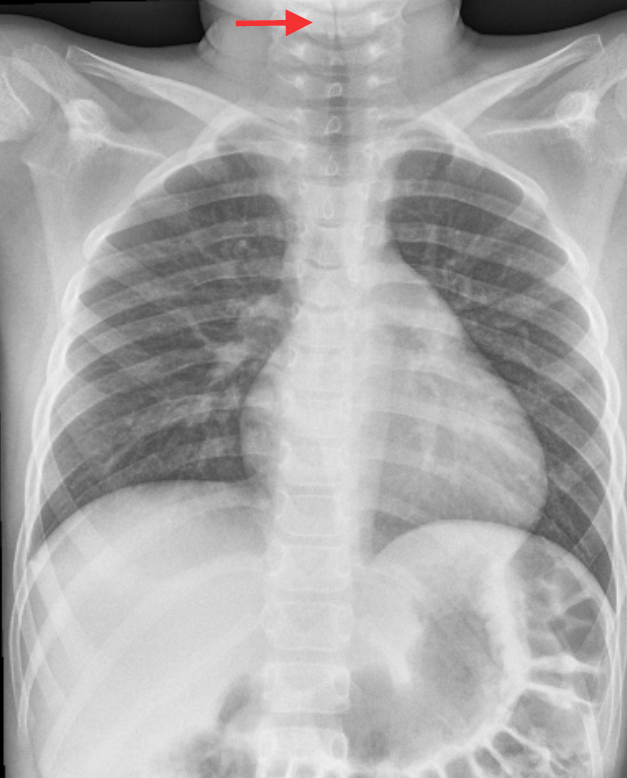

La radiografia del torace è diagnostica: evidenzia chiaramente un restringimento circolare del lume tracheale a livello di C5-C6, compatibile (considerata la clinica) con la diagnosi di tracheite batterica (Figura 1).

La tracheite batterica è responsabile del 5-14% dei ricoveri in Terapia Intensiva per ostruzione delle alte vie respiratorie. È una condizione rara, a esordio estremamente acuto, con necessità di ricorrere all’intubazione fino al 50% dei casi e un modesto rischio di mortalità. In assenza di tracheostomia, generalmente insorge come sovrainfezione batterica in corso di infezione virale (nella popolazione pediatrica complica circa il 2% dei casi di influenza). Dopo l’introduzione del vaccino contro Haemophilus influenzae tipo B, gli agenti eziologici più frequentemente coinvolti sono Staphylococcus aureus, Streptococcus pneumoniae e Haemophilus influenzae non tipizzabile, e il decorso clinico è meno drammatico (tracheite essudativa). Il picco di presentazione è generalmente tra i 3 e gli 8 anni, con quadro clinico generalmente più grave nei più piccoli. Per conferma diagnostica sarebbe necessaria una laringoscopia profonda o una broncoscopia, ma alle volte è sufficiente una radiografia, come nel nostro caso. Talvolta la broncoscopia è indicata con trattamento per rimuovere le pseudomembrane.